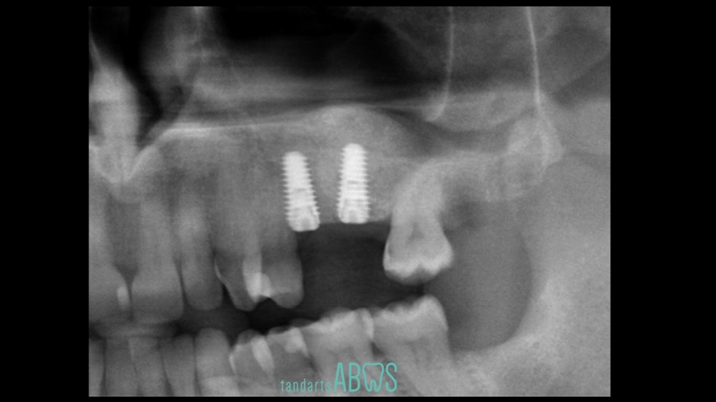

Clinical case: Installation of dental implants in complicated anatomic conditions using crest lifting methods

- Courtesy of Dr.Alexander Lysov, Russia -

AnyRidge, complicated anatomic conditions, crest lift, MICA Kit, Dr. Alexander Lysov, bone regeneration, GBR, #26, maxillary posterior